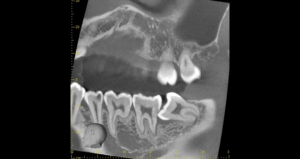

CT

CTで親知らずと神経(下歯槽管)の位置を確認しました。

親知らずと神経は一定の距離があり、麻痺などのリスクがほとんどないと判断できます。

| 抜歯内容 | 左下親知らずが横向きになって半分埋まっている状態だったため、麻酔を行い、親知らずの奥の歯ぐきに切開をいれ、歯が囲んでいる骨を削り、歯の頭の部分を削って出し、その後根の部分に器具をかけて抜歯しました。 親知らずが一部神経に近い部分があったため、術後に麻痺が出る可能性がありました。このケースでは事前にCTを撮影し、歯の位置、根の方向、神経との距離を確認していたため、幸い麻痺が出ることはありませんでした。 術後1週間経過して糸取りをして治療は終了となりました。抜歯後3日間は腫れと痛みで大変だったが、糸取りをする頃には痛みも腫れも無くなったと患者さまも喜んでおられました。 |

| 抜歯内容 | 右下の親知らずは横向きに生えて埋まっているため、麻酔をし親知らずの奥に切開を入れて歯ぐきを開き、歯を囲んでいる骨を削り歯の頭部分を割って出してから、残った根の部分を取り出して抜歯は終了しました。 歯ぐきを切った部分は糸で縫っています。このケースでは根の先端が神経に近く麻痺のリスクがありましたが事前にCTを撮影し、神経との位置関係を確認していたため、麻痺が残ることはありませんでした。 約1週間後に糸取りを行い、その際も多少の痛みや腫れはありましたが後日その痛みも無くなりました。 |

| 抜歯内容 | レントゲン上で右下の親知らずが大きく虫歯になっており、斜めに生えていることもあり患者様の希望により抜歯することとなりました。 当日は痛みがあったため抗生剤と鎮痛剤にて炎症を抑え、後日歯ぐきを切開し、抜歯を行いました。 レントゲン上でも分かるように親知らずの根が二つに分かれており根が折れてしまう可能性がありましたが、このケースでは事前にCTを撮影し、歯の位置、根の方向を確認していたため根が折れることなく抜歯ができました。 術後数日は腫れと痛みがありましたが、薬の服用で抑えることができ、1週間後の糸取りの際には痛み、腫れともになくなっていました。 |

| 抜歯内容 | 当院に通院中の患者様です。 当日は痛みがあったため抗生剤と鎮痛剤にて炎症を抑え、後日歯ぐきを切開し、抜歯を行いました。 下顎の両方とも横向き生えていて、手前の歯も虫歯になっているため抜歯をすることになりました。 麻酔を行い親知らずの奥に切開を入れて、歯を覆っている周りの骨を削りました。 その後歯の頭を削って出して、残った根の部分に器具を引っかけて根の部分を取り出しました。切開した歯ぐきは糸で縫ったため約1週間後に糸取りをして終了となりました。 この症例では、横向きに生えている歯の根の先端が神経に近い場所にあったため、術後のリスクとして知覚の麻痺が出てしまう可能性がありましたが、事前にCTを撮影し、歯の位置、根の方向、神経との位置関係を確認していたため、術後の麻痺など出ることなく経過は良好です。 |

| 抜歯内容 | 矯正治療のために左右の下顎の親知らず抜歯を 希望された患者様です。 親知らずは歯ぐきに覆われて見えていないため、親知らずの手前の歯の奥から切開を入れて歯ぐきを開き、親知らずが見える状態にします。 その後歯を囲んでいる骨を削り、歯を取り出しました。 このケースでは事前にCTを撮影し、歯の位置、神経との位置関係を確認してから抜歯を行っています。 抜歯後、一週間は腫れと痛みがありましたが鎮痛剤を飲んで対応して頂き、糸取りをする頃には痛みや腫れは無くなり、患者様も安心しておられました。 |

| 抜歯内容 | 当院に通院中の患者様です。右下の親知らずが埋まっていて、一部だけ見えてきており、そこが穴になってしまい食べ物が詰まってしまう状態でした。そのため、親知らずに被っている歯肉を切開し、その後、歯の一部が骨で囲まれているため周りの骨を落としました。そして器材を引っかけるところが出来たところで抜歯しました。 この症例では事前にCTを撮影し、歯の根が2本に分かれており、根が曲がっていることが分かっていたため、歯を抜く際に力をかける方向に気をつけて丁寧に抜歯を行い、根が折れることなく抜歯を終えることができました。 |

| 抜歯内容 | 奥の歯が黒くなってきたとのことで来院された患者様です。親知らずが横向きに生えており、一部見えている部分が虫歯になっている状態でした。まずは見えている親知らずの奥に切開を入れ、歯の周りを覆っている骨を削り、歯の頭の部分を分割して歯の根の部分に器具を引っかけて抜歯を行いました。 この症例では事前にCTを撮影し、歯の位置、根の方向、神経との位置関係を確認していたため、麻痺などの後遺症も出ることなく経過は良好です。抜歯後、数日は痛みがありましたがその後痛みもなくなり、患者様も喜んでおられました。 |